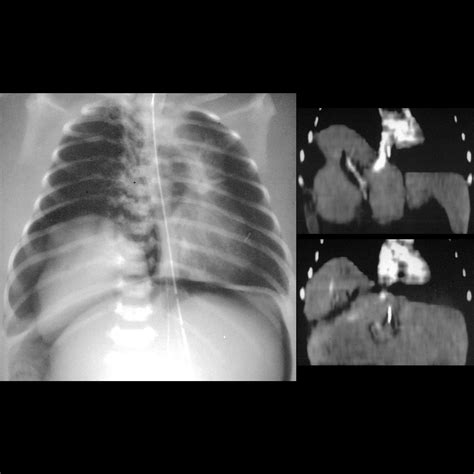

• Computed Tomography (CT): Provides detailed cross-sectional views, used when high-definition structural information is required.

CT Scan Moderate Complex trauma, internal injuries, detailed anatomy